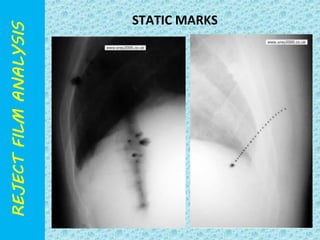

STATIC MARK

STATIC MARKS